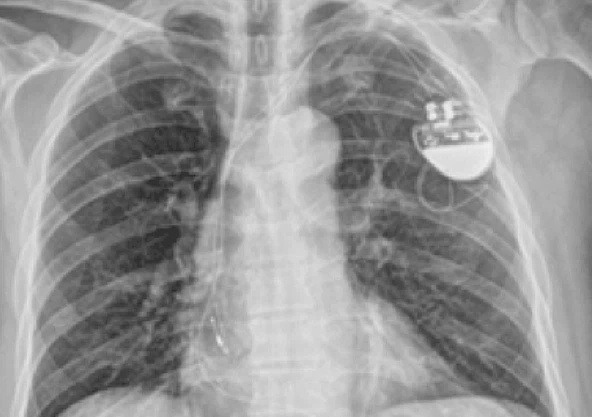

인공심박동기(Pacemaker)란?

인공심박동기는 서맥(너무 느린 심장박동)의 치료로 사용되는 기계입니다. 체내에 삽입된 후 자동으로 심장리듬을 모니터하며 서맥이나 동정지가 발생할 시 정상 맥박수 이상으로 심장이 뛸 수 있게 전기 자극을 주는 역할을 합니다.